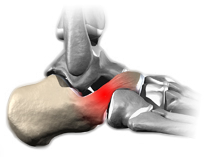

Coalizão Calcâneonavicular

A coalizão calcâneonavicular é a fusão entre o calcâneo e o navicular.

Normalmente ocorre na porção superior e frontal do calcâneo, chamada de processo anterior, com a borda medial e inferior do osso navicular.

Os sintomas iniciam por volta dos 8 anos de idade.